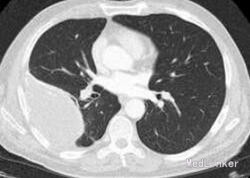

患者:男性,68 岁,出现咯血、胸痛,偶有发冷;无发热、体重减轻和呼吸困难。该患者童年有结核病病史,未接受抗结核治疗,后右下胸膜出现胸膜钙化且保持稳定。

胸部 CT 显示右下肺后段胸膜处有一 5.5x4.5cm 不透明的低密度影和多个非钙化肺结节(直径≤4 毫米)及纤维条索和隆突下淋巴结钙化。